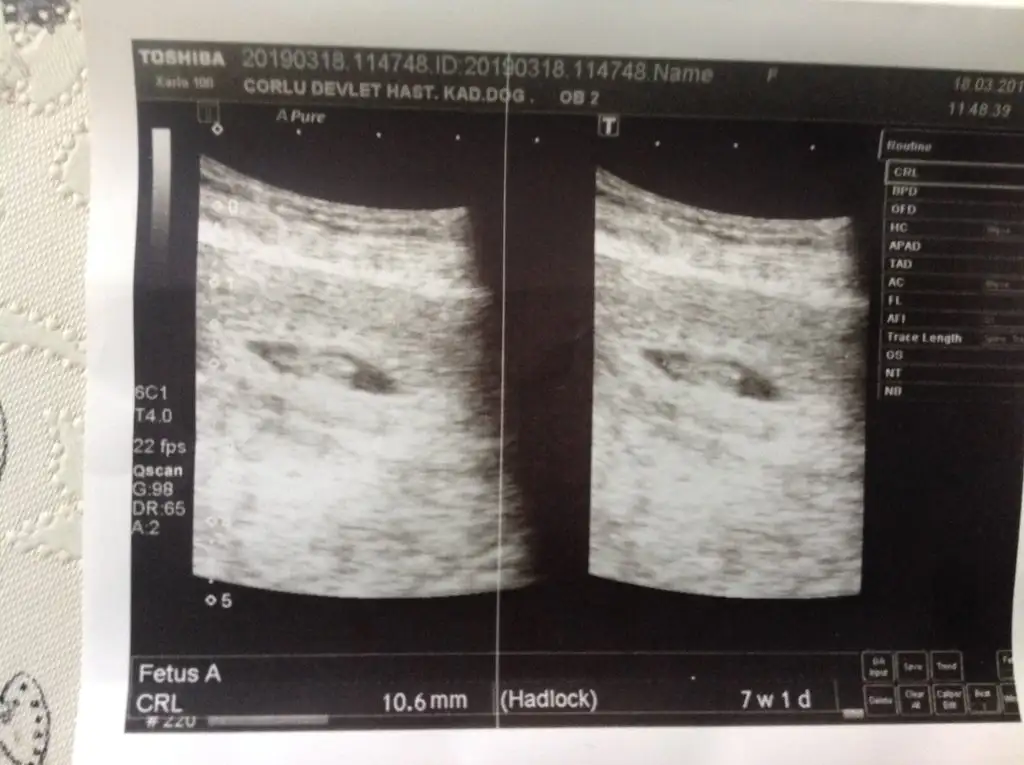

Kızlar bu resimde 7+1 ama ultrasonda 7+3. Ben anlamadım, sizce nedir cinsiyet? :))

Eklentiler

• IMG_20190326_154522.webp

IMG_20190326_154522.webp

32,6 KB · Görüntüleme: 63

• IMG_20190326_154451.webp

IMG_20190326_154451.webp

28,4 KB · Görüntüleme: 49